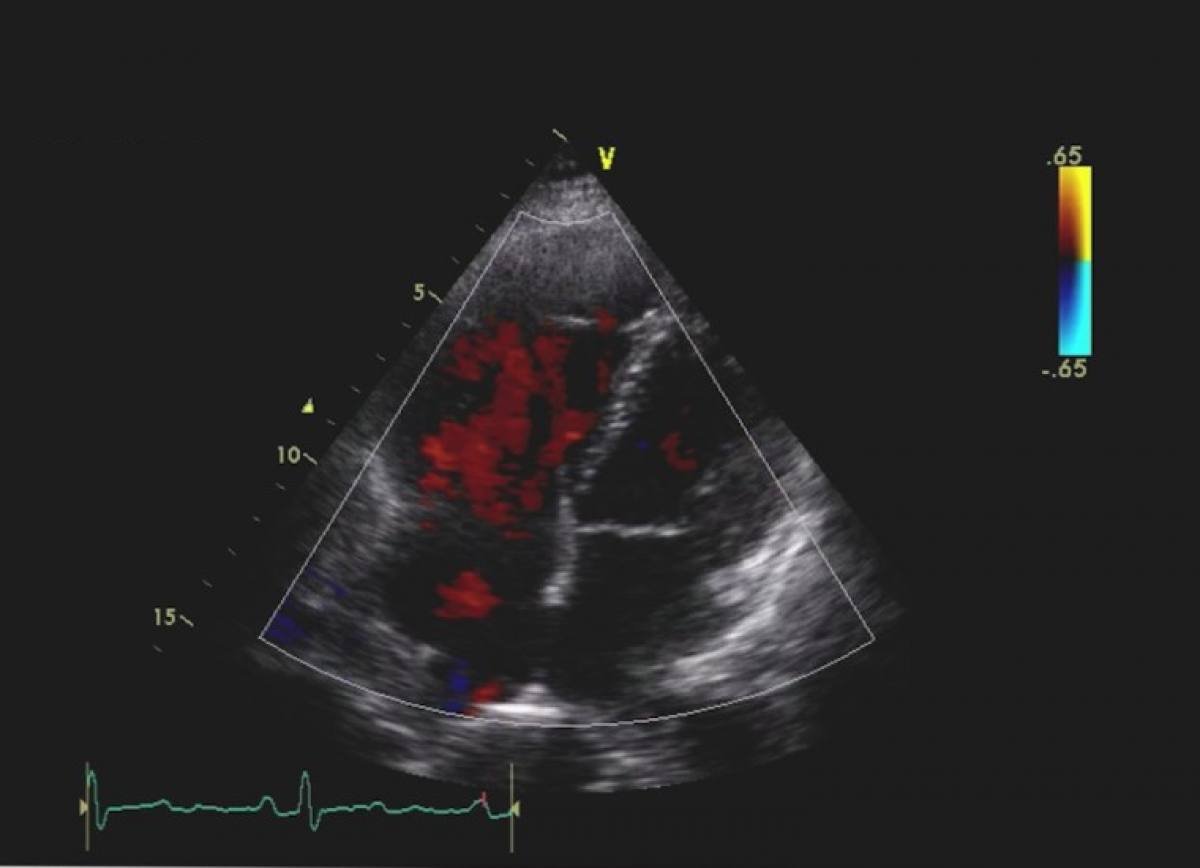

Niedomykalność mitralna na tle wypadania płatków zastawki mitralnej.

Ocena niedomykalności mitralnej.